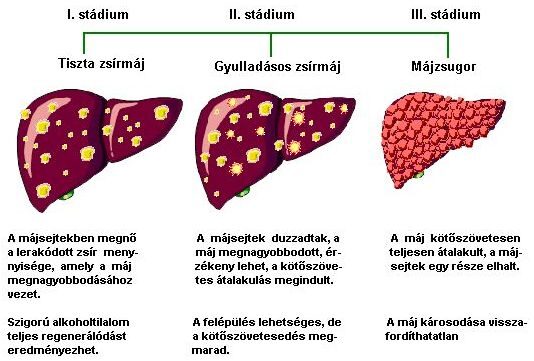

Sokkal gyakoribbak a máj krónikus betegségei. Hazánkban sajnos a leggyakoribb oka az alkoholfogyasztás, esetleg egyéb májkárosodást okozó eltéréssel együtt. Ebben a vonatkozásban az a legnagyobb baj, hogy az alkoholfogyasztás mértékével kapcsolatban az általános nézetek tévesek. Nem csak annak lehet alkoholos májbetegsége, aki részeg szokott lenni. Egyéni érzékenységtől, testsúlytól és az alkohol minőségétől függően napi 1-1,5 dl tömény alkohol, vagy ennek megfelelő kb. 1,5 liter sör, vagy 1 liter bor napi rendszerességgel elfogyasztva éveken át, az emberek legnagyobb részében akkor is okozhat alkoholos szervi betegséget, ha az illető soha nem volt részeg.

| Az alkoholos májbetegség három stádiuma |

A krónikus májbetegség kifejezett és típusos tünetet előrehaladott stádiumban okoz. Minden krónikus májártalmat okozó betegség végstádiuma a májzsugor. Ez a máj működő sejtjeinek jelentős fokú elvesztését jelenti, helyette kötőszövet halmozódik fel. Ennek két következménye lesz. Az egyik, hogy a máj minden funkciója romlik, valamint a bél felől érkező vér elfolyása a máj felé nehezített lesz. A funkcióvesztés következtében sárgaság jelenik meg, a vizelet sötétté válik. Romlik a máj fehérjeszintézise. Emiatt kezdetben az izomzat fehérjéinek felhasználása miatt a karok, lábak elvékonyodnak. Később a vérben keringő fehérjék hiánya miatt a beteg lába vizenyőssé, duzzadttá válik.